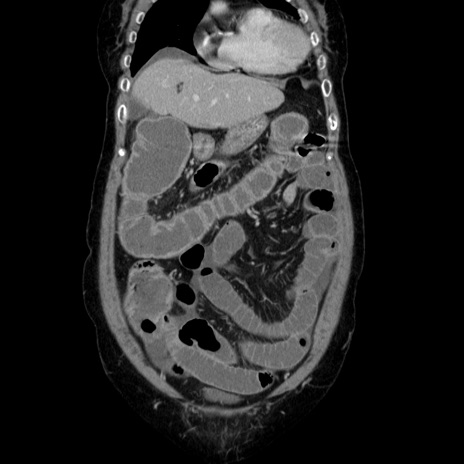

横断像

【症例】70歳代女性

【主訴】お腹が張る

【現病歴】1週間くらい前から腹部膨満の自覚あり。昨日夜から増悪したため、本日救急外来受診。

【身体所見】意識清明、BT 36.5℃、BP 165/106mmHg、HR 80bpm、SpO2 98%、腹部:膨満、軟、自発痛・圧痛なし、触診にて不快感あり、腸蠕動音:減弱

【データ】WBC 12600、CRP 1.04